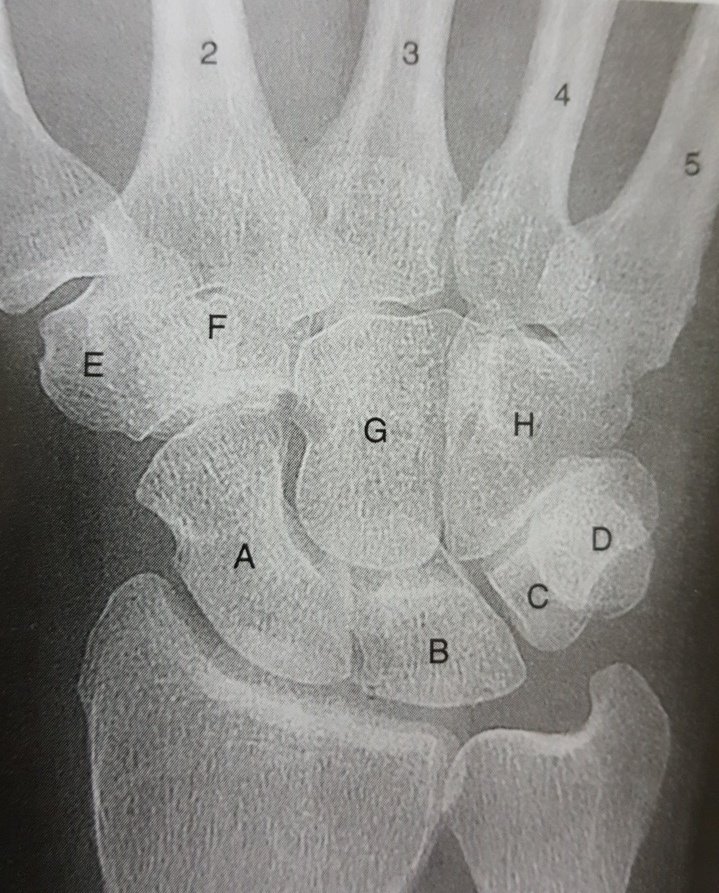

يتكون من ٨ عظيمات : ٤في الصف الأمامي و ٤ في الصف الخلفي.

أكثرها تعرضاً للكسر :

Scaphoid

معلومة عن هذه العُظيمة:

في بعض الأحيان تسمى navicular

نفس اسم العظيمة الموجودة في القدم.